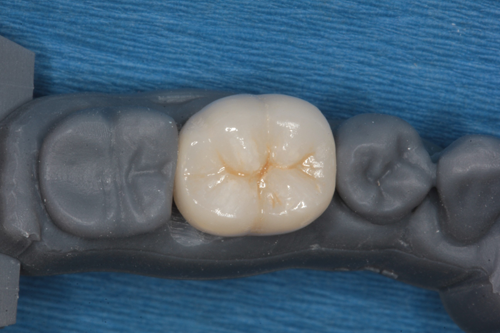

The crown can be seen designed on the model from the facial view in Figure 6 and occlusal view in Figure 7. The crown was milled and Peter added surface staining for esthetics. The final restoration can be seen on a mirrored surface in Figure 8.

Fig. 7 Fig. 8

While not a necessary step, Peter fabricated a 3D-printed model of the teeth to verify the fit and occlusion. In Figure 9 the printed model is shown and the crown is seated on the model in Figure 10.

Fig. 9 Fig. 10